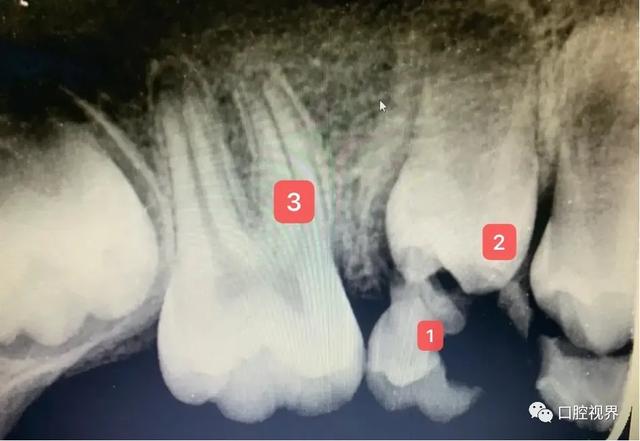

如图中标记1所示,龋齿乳牙可以被完全吸收,无需治疗就可以直接拔除。

如图2所示,待萌出恒牙的牙根尚处于发育阶段,但即将从牙龈中萌出,提示与上乳牙根尖周改变有关。(我从牙片中更直观地感受到为什么牙医要强调乳牙健康的重要性)。

如图中标记3所示,第一颗几乎发育完全的恒牙(六岁牙),牙冠最大,咀嚼能力最强,最早。

萌出的大牙。要好好保护好。